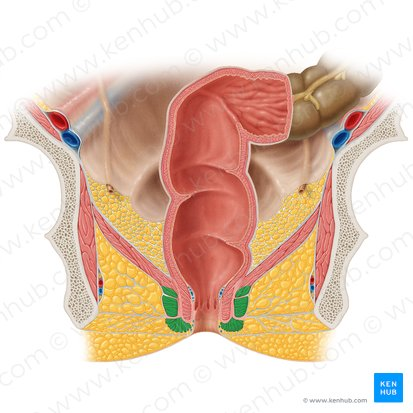

Rectum

the final section of the large intestine, terminating at the anus, that stores feces before elimination.

Anus

Internal Anal Sphincter

A thickened ring of smooth muscle that surrounds the anal canal. It is under involuntary control, meaning you don't consciously control its contraction or relaxation. It is normally contracted to maintain fecal continence.

Rectum

The final section of the large intestine, terminating at the anal canal. Its primary function is to store feces before they are eliminated from the body.

External Anal Sphincter

A ring of skeletal muscle that surrounds the anal canal, superficial to the internal anal sphincter. It is under voluntary control, meaning you can consciously choose to contract or relax it to control the passage of feces. This allows for the postponement of defecation.

Anus

The opening at the end of the digestive tract through which feces are eliminated from the body. It is surrounded by the internal and external anal sphincters, which regulate the passage of waste.